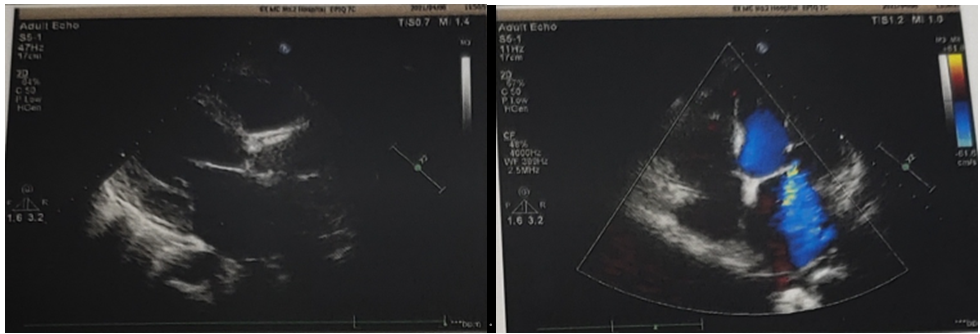

术前心超示:

峰值流速:2.1 m/s

最高跨瓣压差:17.6 mmHg

平均跨瓣压差:12.3 mmHg

左室射血分数EF值:0.6

左室舒张末期内径(LVD):54 mm

主动脉瓣评估:左房、左室增大,主动脉瓣增厚,回声增强,可见钙化,右冠瓣活动僵,瓣口收缩期血流流速增快,瓣口舒张期可见反流。